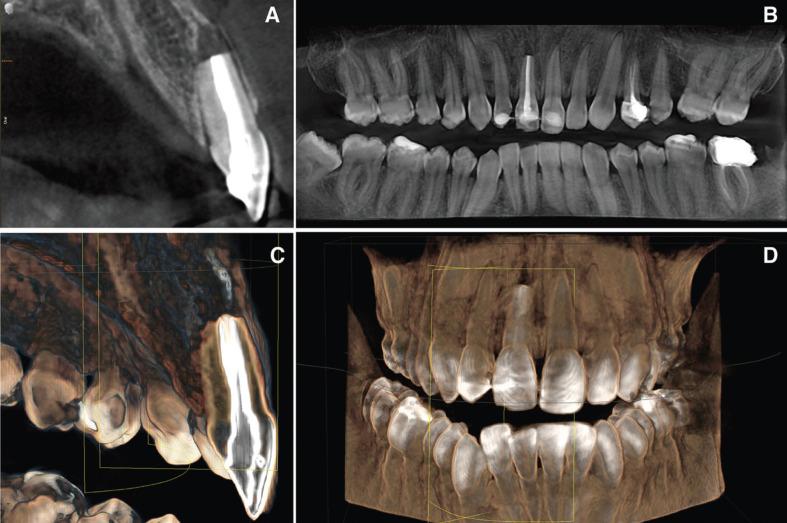

This report describes a case of a 28 year-old male who suffered contusion of the upper lip, avulsion of right upper central incisor, enamel cracks after trauma of left upper central incisor and upper left lateral incisor crown fracture due to an accident. Avulsed tooth was dry stored and it was replanted 16h after the trauma. The root was disinfected and the necrotic periodontal tissue removed, the endodontic treatment was done before replantation and a flexible splint was applied to tooth 13 to tooth 23. Two months later a contralateral tooth presented crown discoloration occurred due to pulp necrosis an endodontic treatment as well as bleaching were carried out. An esthetic restoration for lateral incisor crown fracture was also done. In the one year review the patient remains asymptomatic, with no signs of root resorption or ankylosis of the damaged teeth.

本报告描述了一名28岁男性的病例,该患者因意外事故导致上唇挫伤、右上中切牙撕脱、左上中切牙外伤后釉质裂纹以及左上侧切牙冠折。撕脱牙进行了干燥保存,并在创伤后16小时进行了再植。对牙根进行了消毒,去除了坏死的牙周组织,在再植前进行了根管治疗,并对13至23号牙应用了弹性夹板。两个月后,对侧牙齿因牙髓坏死出现冠变色,进行了根管治疗和漂白。还对侧切牙冠折进行了美学修复。在一年的复查中,患者无症状,受损牙齿无牙根吸收或粘连迹象。